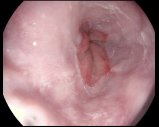

4.1.7 Gastrointestinal endoscopy

Endoscopies are used to detect diseases in the human digestive system. Images from inside the gastrointestinal tract can help physicians detect diseases early. The used dataset 777https://www.kaggle.com/datasets/abdallahwagih/kvasir-dataset-for-classification-and-segmentation contains eight image categories of the digestive system obtained through the endoscopy imaging technique, as shown in Fig. 8. There are a total of images that can be used in training and testing ML algorithms.